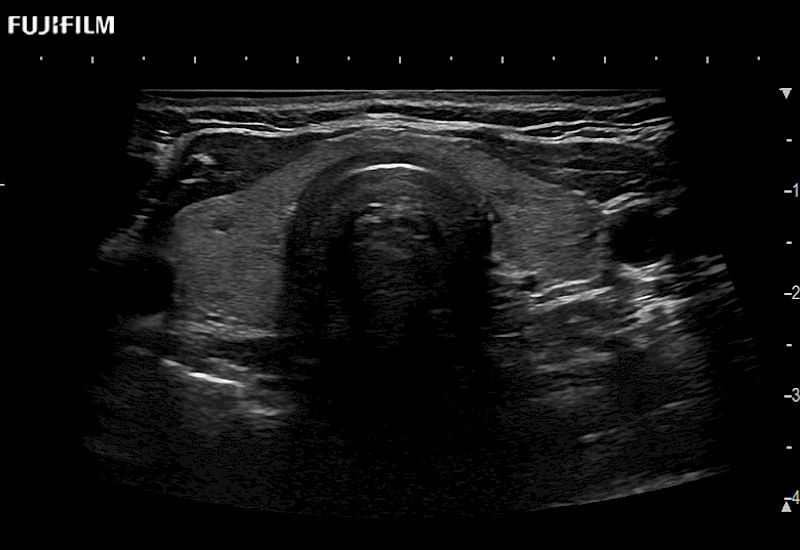

The ARIETTA 750 incorporates all of the proven technologies and functions that medical professionals have come to expect from Fujifilm Healthcare.

ARIETTA 750 is the definitive diagnostic ultrasound solution for any clinical setting - Private Office, Imaging Center, or Hospital. The ARIETTA platform provides the ultimate in clinical performance with its state-of-the-art features and large user-friendly display.

The ARIETTA 650 DI combines trusted Fujifilm Healthcare technologies and features tailored for surgical oncology.

Designed to meet the demands of surgeons, the ARIETTA 650 DI offers precise guidance. Its advanced capabilities and large, intuitive display offer accurate and efficient care in operating rooms and specialized surgical settings.